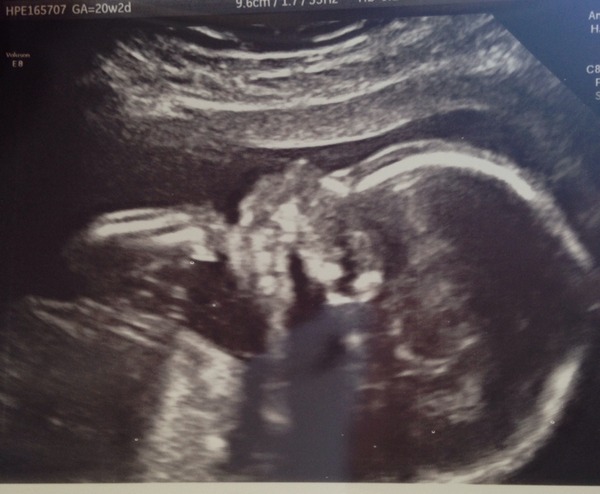

All was well with our little boy, he doesn't like the cold gel, and now I've realised the kicks near my belly button are actually him elbowing me! He did it on screen and I felt it really hard. Measuring fine and all healthy, he had his hand in his mouth too Covent, you can see his arm just up towards his face.